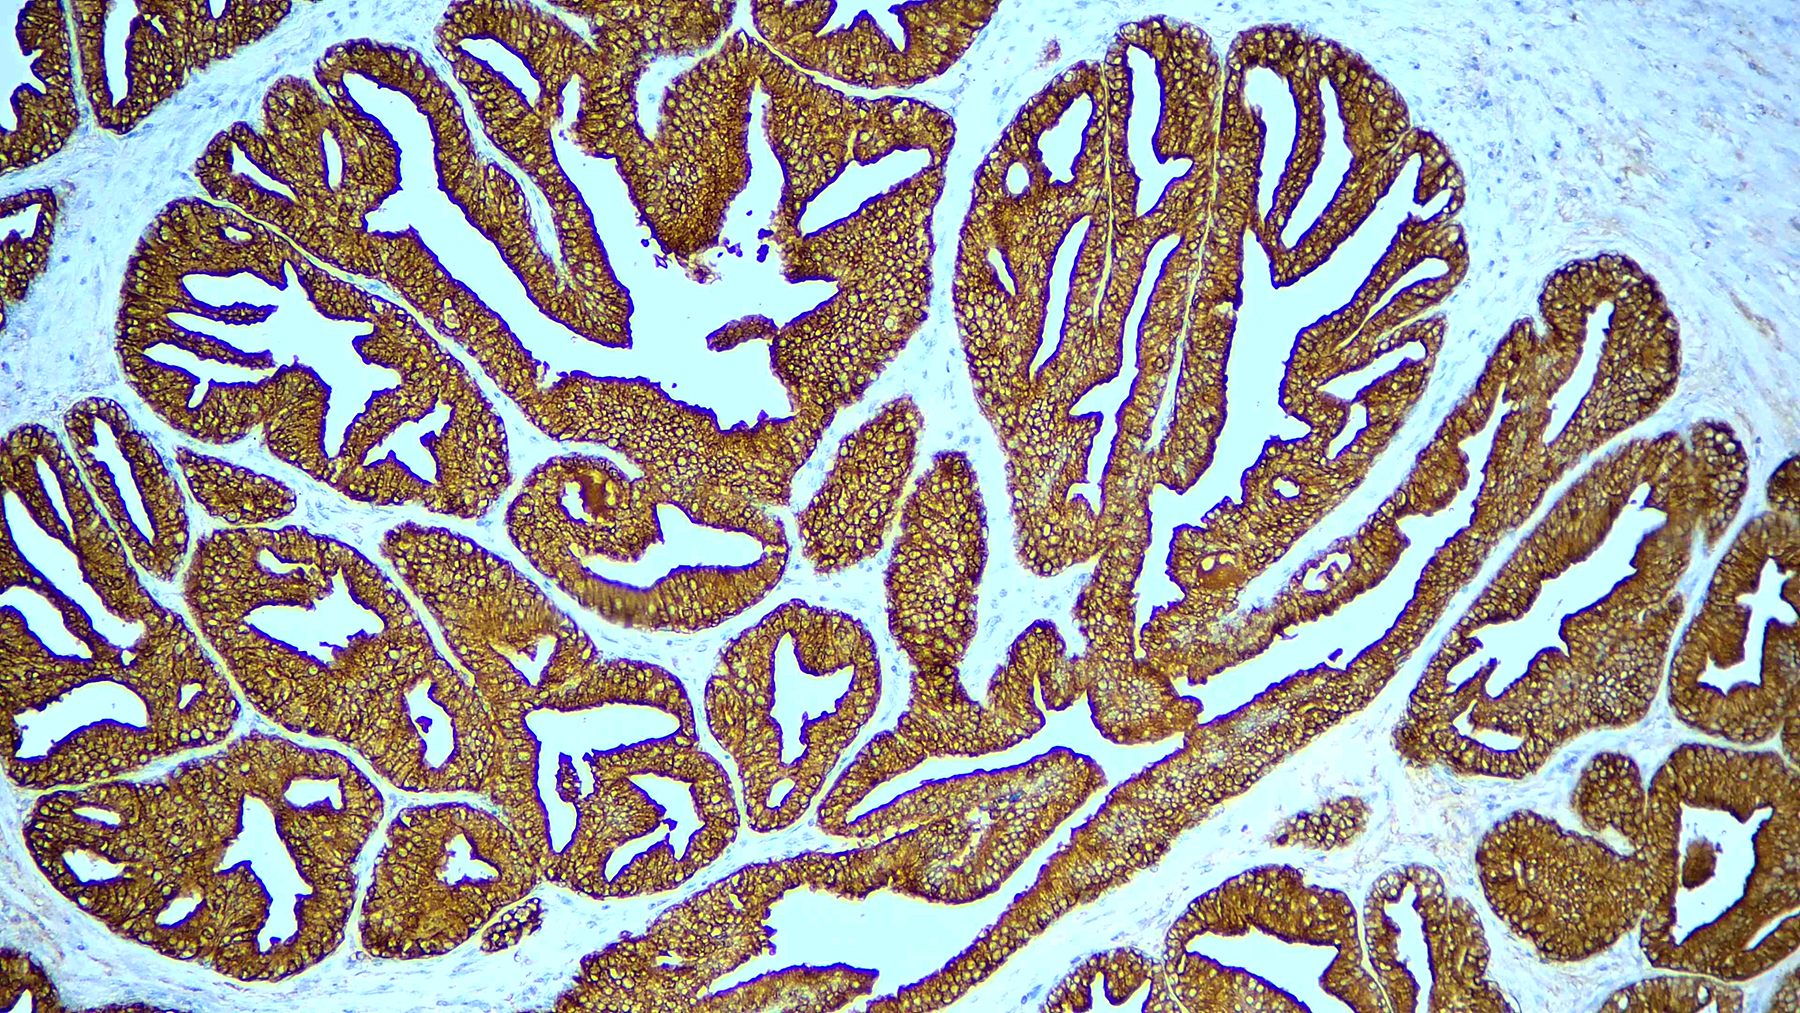

Prostate Specific Antigen, PSA

This product is intended for qualitative immunohistochemistry with normal and neoplastic formalin-fixed, paraffin-embedded tissue sections, to be viewed by light microscopy. Clinical interpretation of staining results should be accompanied by histological studies with proper controls. Patients’ clinical histories and other relevant diagnostic tests should be utilized by a qualified person(s) when evaluating and interpreting results.

| Immunogen | Prostate specific antigen isolated from human seminal plasma. |

| Positive Control Tissue | Prostate carcinoma |